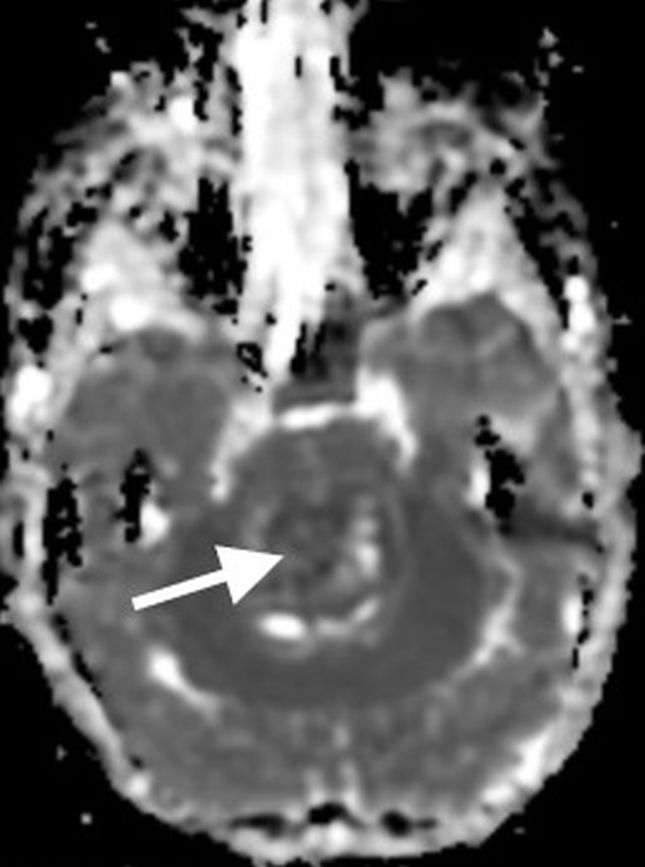

On MR imaging, DMGs present as a diffuse, ill-defined, T2 hyperintense, expansile masses centered within the pons. The degree of enhancement is variable, often absent at initial presentation and typically patchy when present (Fig. 3).

Peripheral enhancement commonly occurs along margins of central necrosis, which occurs more frequently after radiation therapy [25]. Intralesional hemorrhage is uncommon, but areas of hemosiderin deposition may be seen on susceptibility-weighted sequences. Focal areas of restricted diffusion develop in the majority of cases. The presence of central necrosis, diffusion restriction, or enhancement at the time of initial diagnosis has been shown to portend a worse prognosis [24].